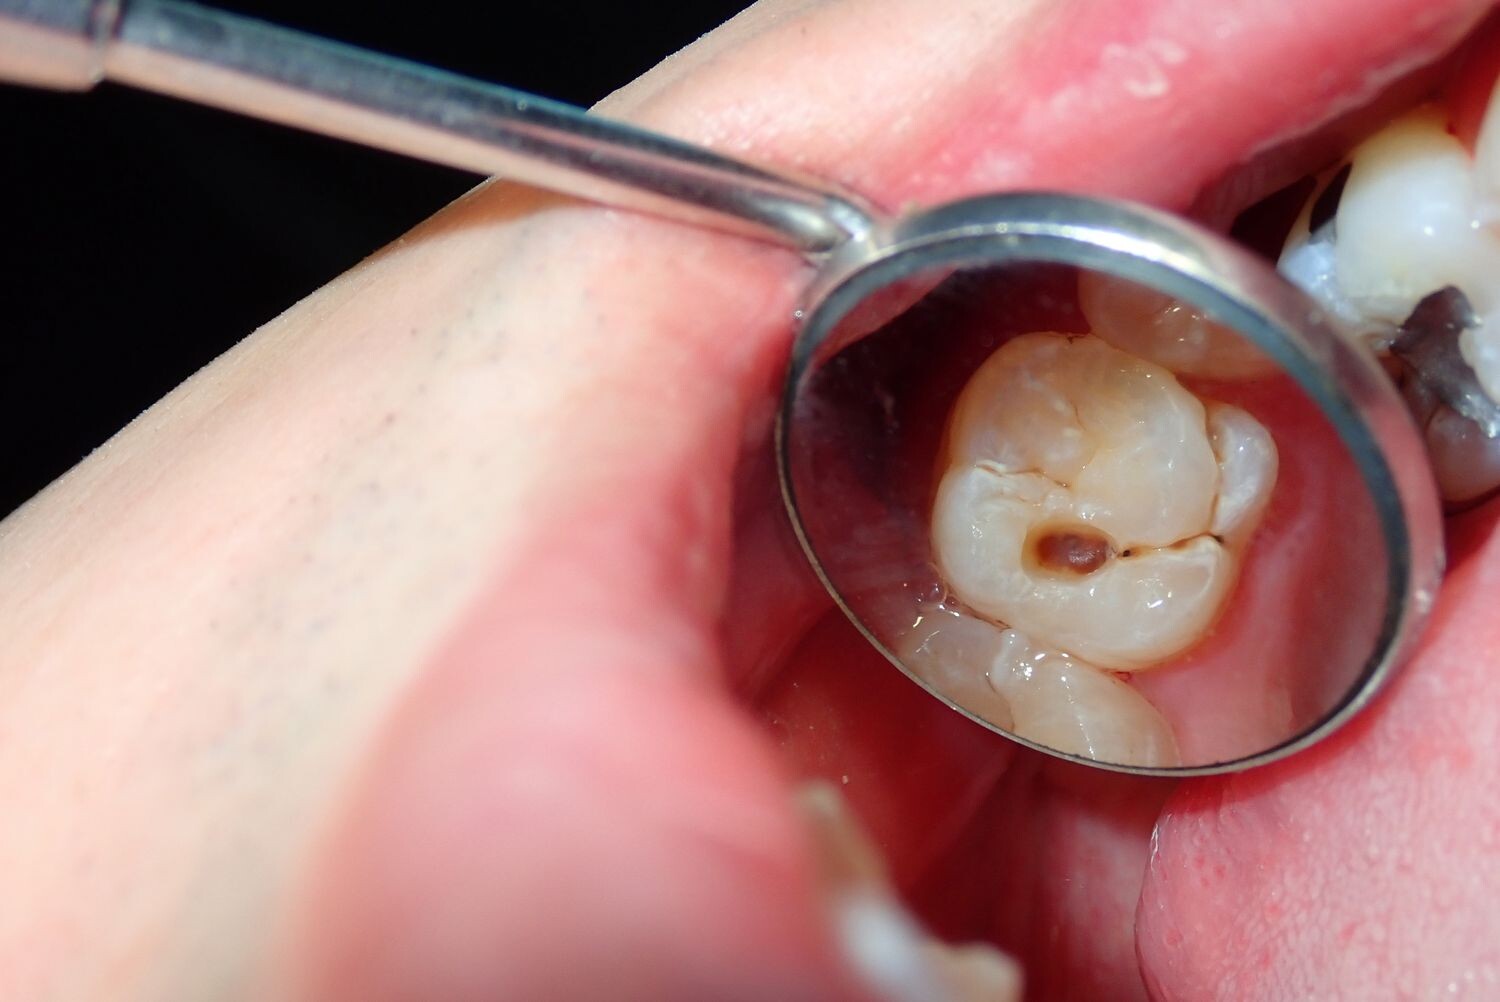

Cavities are pretty common. As the National Institutes of Health points out, the only condition more common than a cavity is the common cold. If you've never experienced tooth decay, you might wonder, "What does a cavity feel like?" The answer depends on the stage of the cavity and what foods you eat. Some foods, such as sweets, might trigger the pain of a cavity more than others.

How Cavities Form

Your mouth is naturally full of germs. Some of those germs are perfectly healthy, but others can be harmful. When you eat something sugary, such as candy or even potato chips, or drink a sugary beverage, the germs feed on the sugars in the substance. This produces acid, which is strong enough to wear away tooth enamel if not cleaned off quickly enough. In the end, a dental cavity begins to form.

In the early stages, a cavity can be reversed, as the National Institute of Dental and Craniofacial Research notes. Brushing your teeth with a toothpaste that contains fluoride can help restore the enamel and reverse the effects of cavities.

Signs of a Cavity

What does a cavity feel like? In the earliest stages, the answer might be nothing. There are no nerves in your tooth enamel, so when the decay is in that layer, you likely won't feel a thing. Once the decay has progressed enough to reach the softer tissues inside the tooth, where the dentin and nerves are, you might notice signs of a cavity. Your teeth might feel sensitive and you could feel some pain, especially after eating sweets, hot foods or cold foods. The pain can be fairly mild or sharp and intense. Some people with cavities also feel pain when biting down.

Depending on the size of the cavity, you may be able to see evidence of it in your mouth. Cavities sometimes create visible holes in the teeth. They can also create stains that are black, brown or white on the surface of the tooth.

Cavities and Sweets

Why are you more likely to feel pain from a cavity when you eat sweets? Some foods, including sweets, are more likely to cause pain when there is enamel erosion. Sweet foods tend to be sticky, so they often cling to your teeth. The germs that feed on them can then produce more acid, which can make its way into the cavity, irritating the nerves. Even if you don't have a cavity, sugary foods will cause more sensation in sensitive teeth.